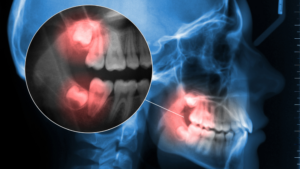

Two nerves in your lower jaw sit in close proximity to the roots of your lower wisdom teeth. These are the inferior alveolar nerve and the lingual nerve, and their location is one of the most important factors we assess before any extraction.

The inferior alveolar nerve runs through a canal inside your lower jawbone. It provides sensation to your lower teeth, lip, and chin. When wisdom tooth roots sit very close to this canal, or wrap around it, extractions carry a higher risk of nerve contact.

Traditional dental X-rays provide a two-dimensional view of your teeth and jaw. They can show that a wisdom tooth root is near the nerve canal, but they can’t show exactly how close, or in which direction the root curves.

Cone beam computed tomography (CBCT) imaging changes this entirely. CBCT creates detailed 3D images of your teeth, roots, nerves, and bone, showing us the exact spatial relationship between wisdom tooth roots and nerve canals from every angle.